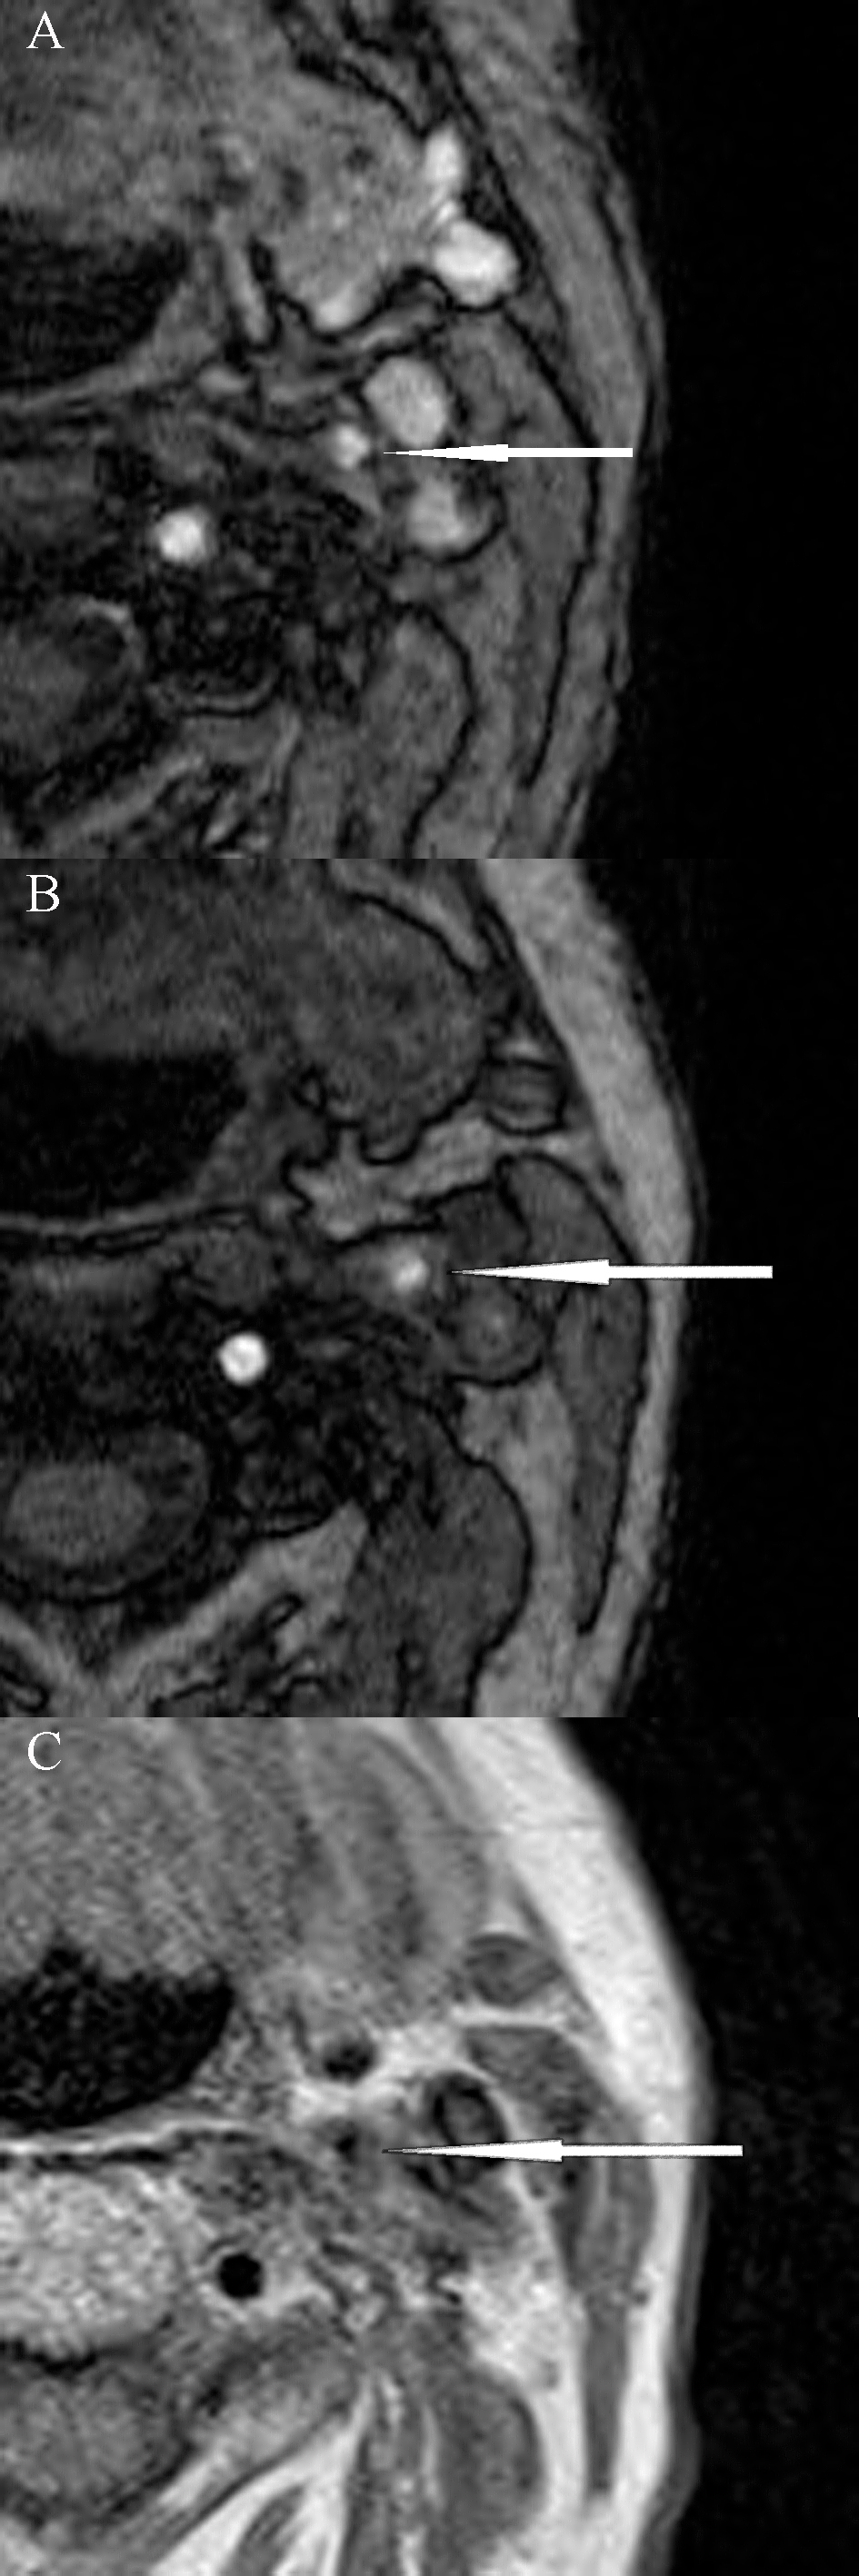

Components of carotid atherosclerotic plaque can be analysed preoperatively by non-invasive advanced imaging modalities such as magnetic resonance imaging (MRI). The expression of matrix metalloproteinase-9 protein (MMP-9), which has a potential role in remodelling of atherosclerotic plaques, can be analysed immunohistochemically. The aim of the present prospective pilot study is to analyse histological characteristics and expression of MMP-9 in carotid plaques of patients undergoing carotid endarterectomy (CEA) and to investigate the correlation with preoperative clinical symptoms and MRI features. Preoperative clinical assessment, MRI imaging, postoperative histological and immunohistochemical analyses were performed. Fifteen patients with symptomatic (7/15; 47%) and asymptomatic carotid artery stenosis undergoing CEA were included. Among symptomatic patients, 5 (71%) had recent stroke and 2 (29%) had recent transient ischaemic attack with a median timing of 6 weeks (IQR: 1, 18) before the surgery. Both groups did not significantly differ in respect to preoperative characteristics. Prevalence of unstable plaque was higher in symptomatic than asymptomatic patients, although it was not significant (63% vs. 37%, p = 0.077). The expression of MMP-9 in CD68 cells within the plaque by semiquantitative analysis was found to be significantly higher in symptomatic as compared to asymptomatic patients (86% vs. 25% with the highest expression, p = 0.014). The average microvascular density was found to be higher and lipid core area larger among both symptomatic patients and unstable carotid plaque specimens, although this did not reach statistical significance (p = 0.064 and p = 0.132, p = 0.360 and p = 0.569, respectively). Our results demonstrate that MRI is reliable in classifying carotid lesions and differentiating unstable from stable plaques. We have also shown that the expression of MMP-9 is significantly higher among symptomatic patients undergoing CEA.